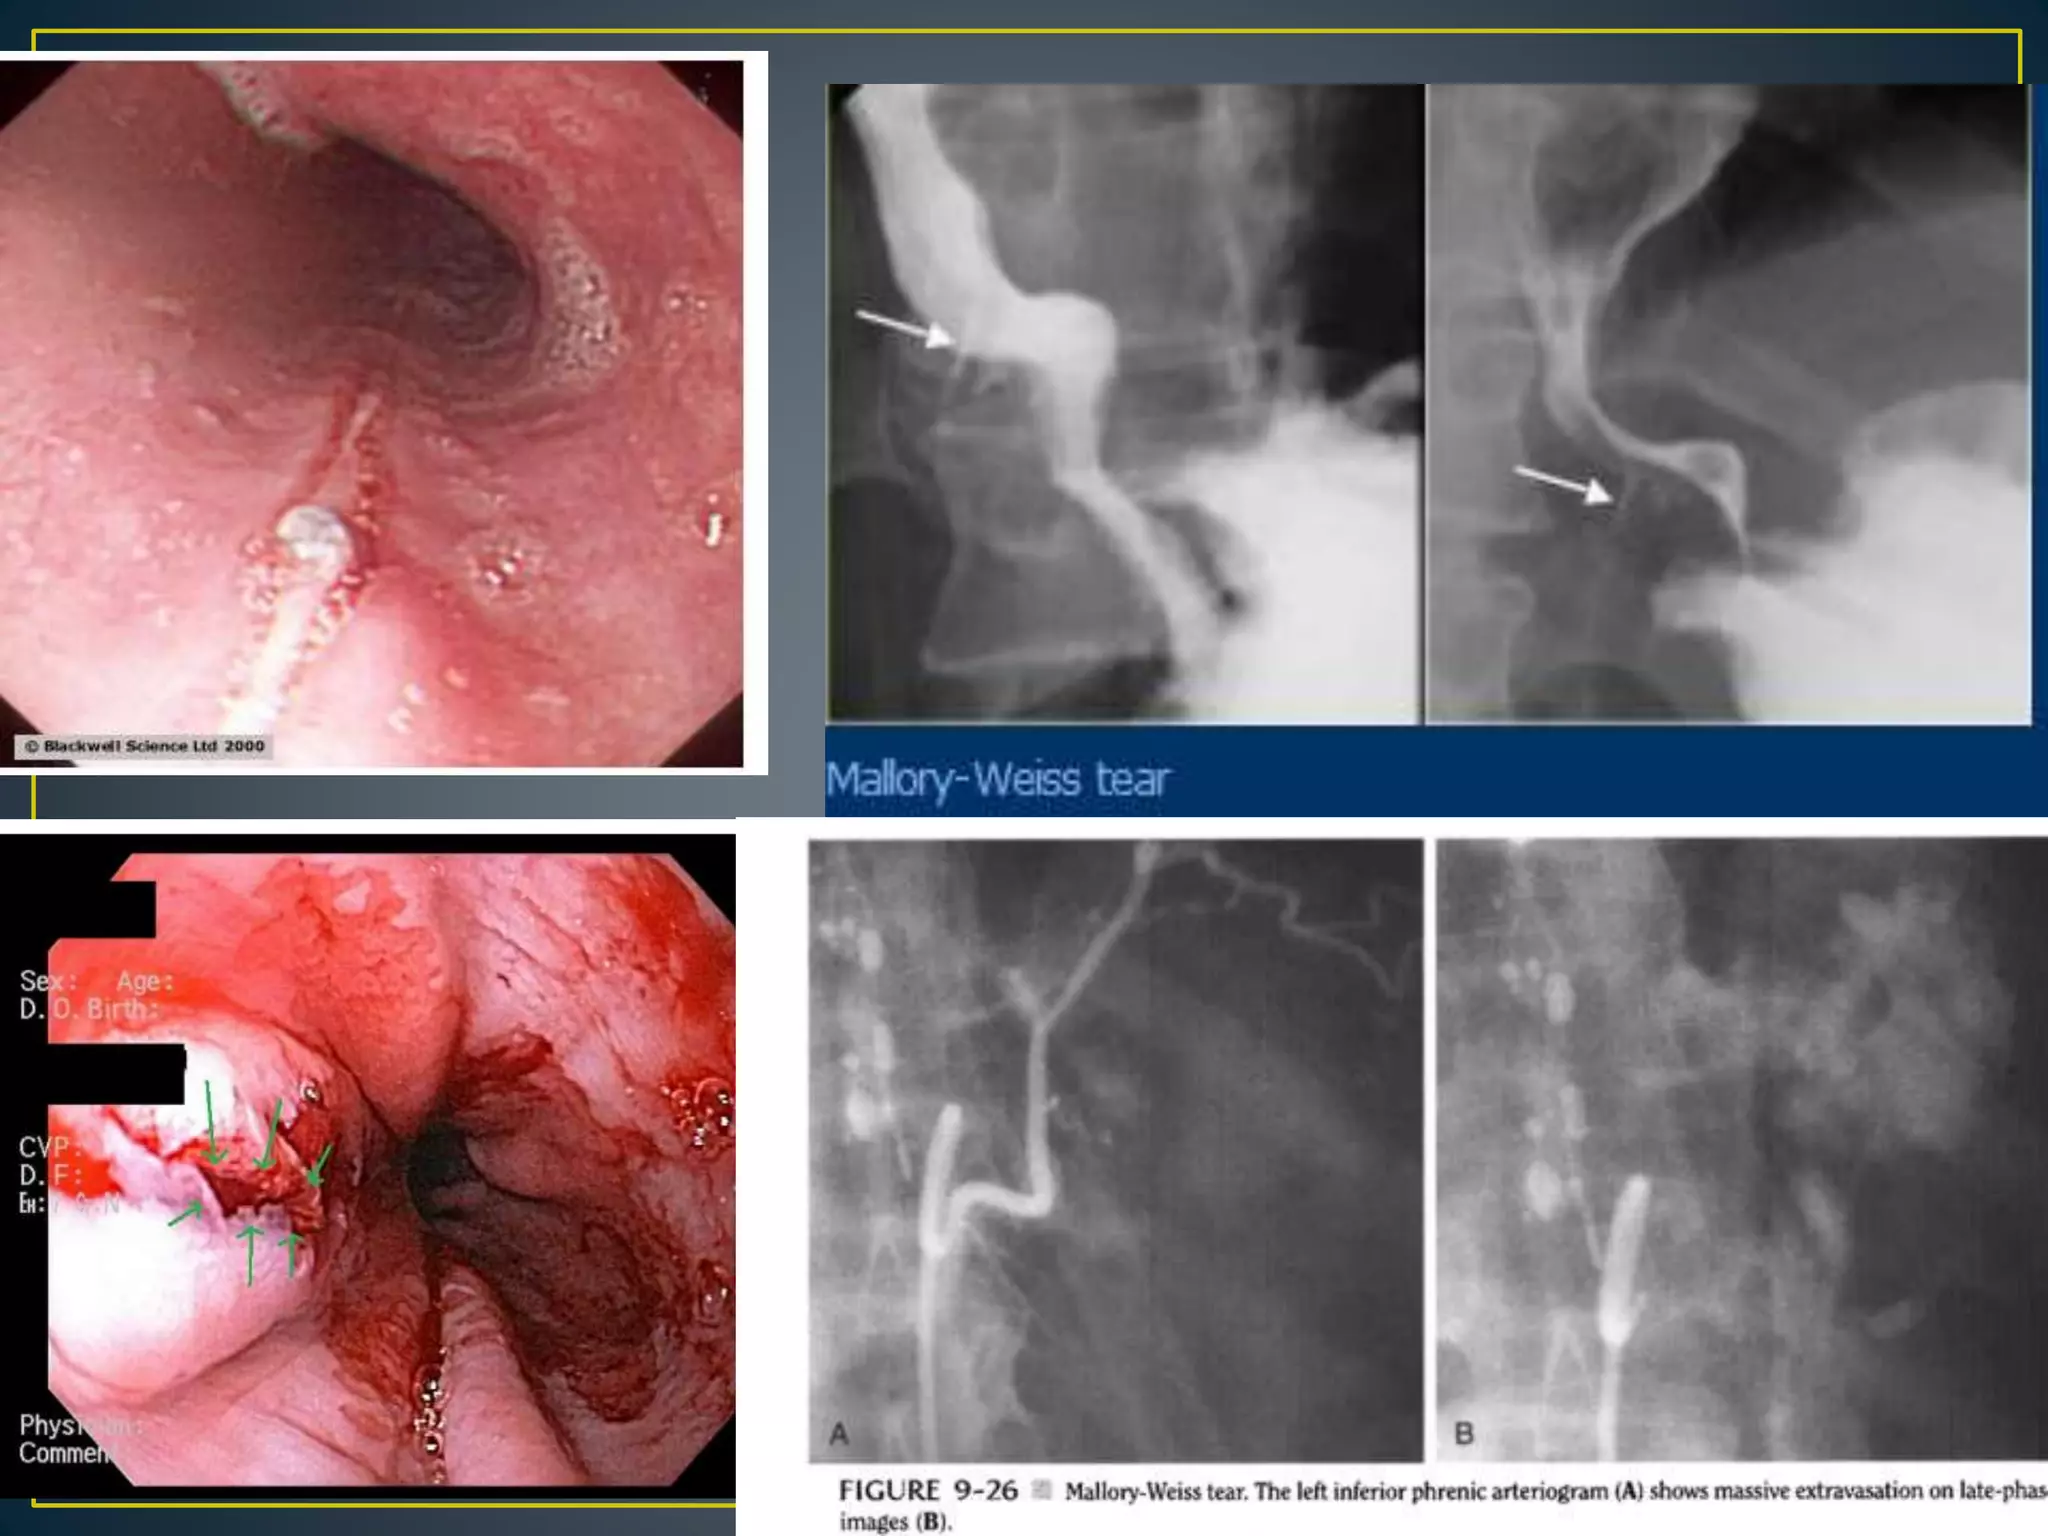

• The lesion is characterized by a tear in the proximal

gastric mucosa near the esophagogastric junction.

The clinical presentation is typified by an antecedent

history of vomiting, retching, or coughing followed

by hematemesis. The mean age for patients with this

condition is older than 60 years; 80% are men.

• Up to 90% of these lesions stop bleeding

spontaneously without specific intervention. Patients

with cirrhosis and portal hypertension with

coagulopathy are at greatest risk for morality, which

overall averages 3%.[